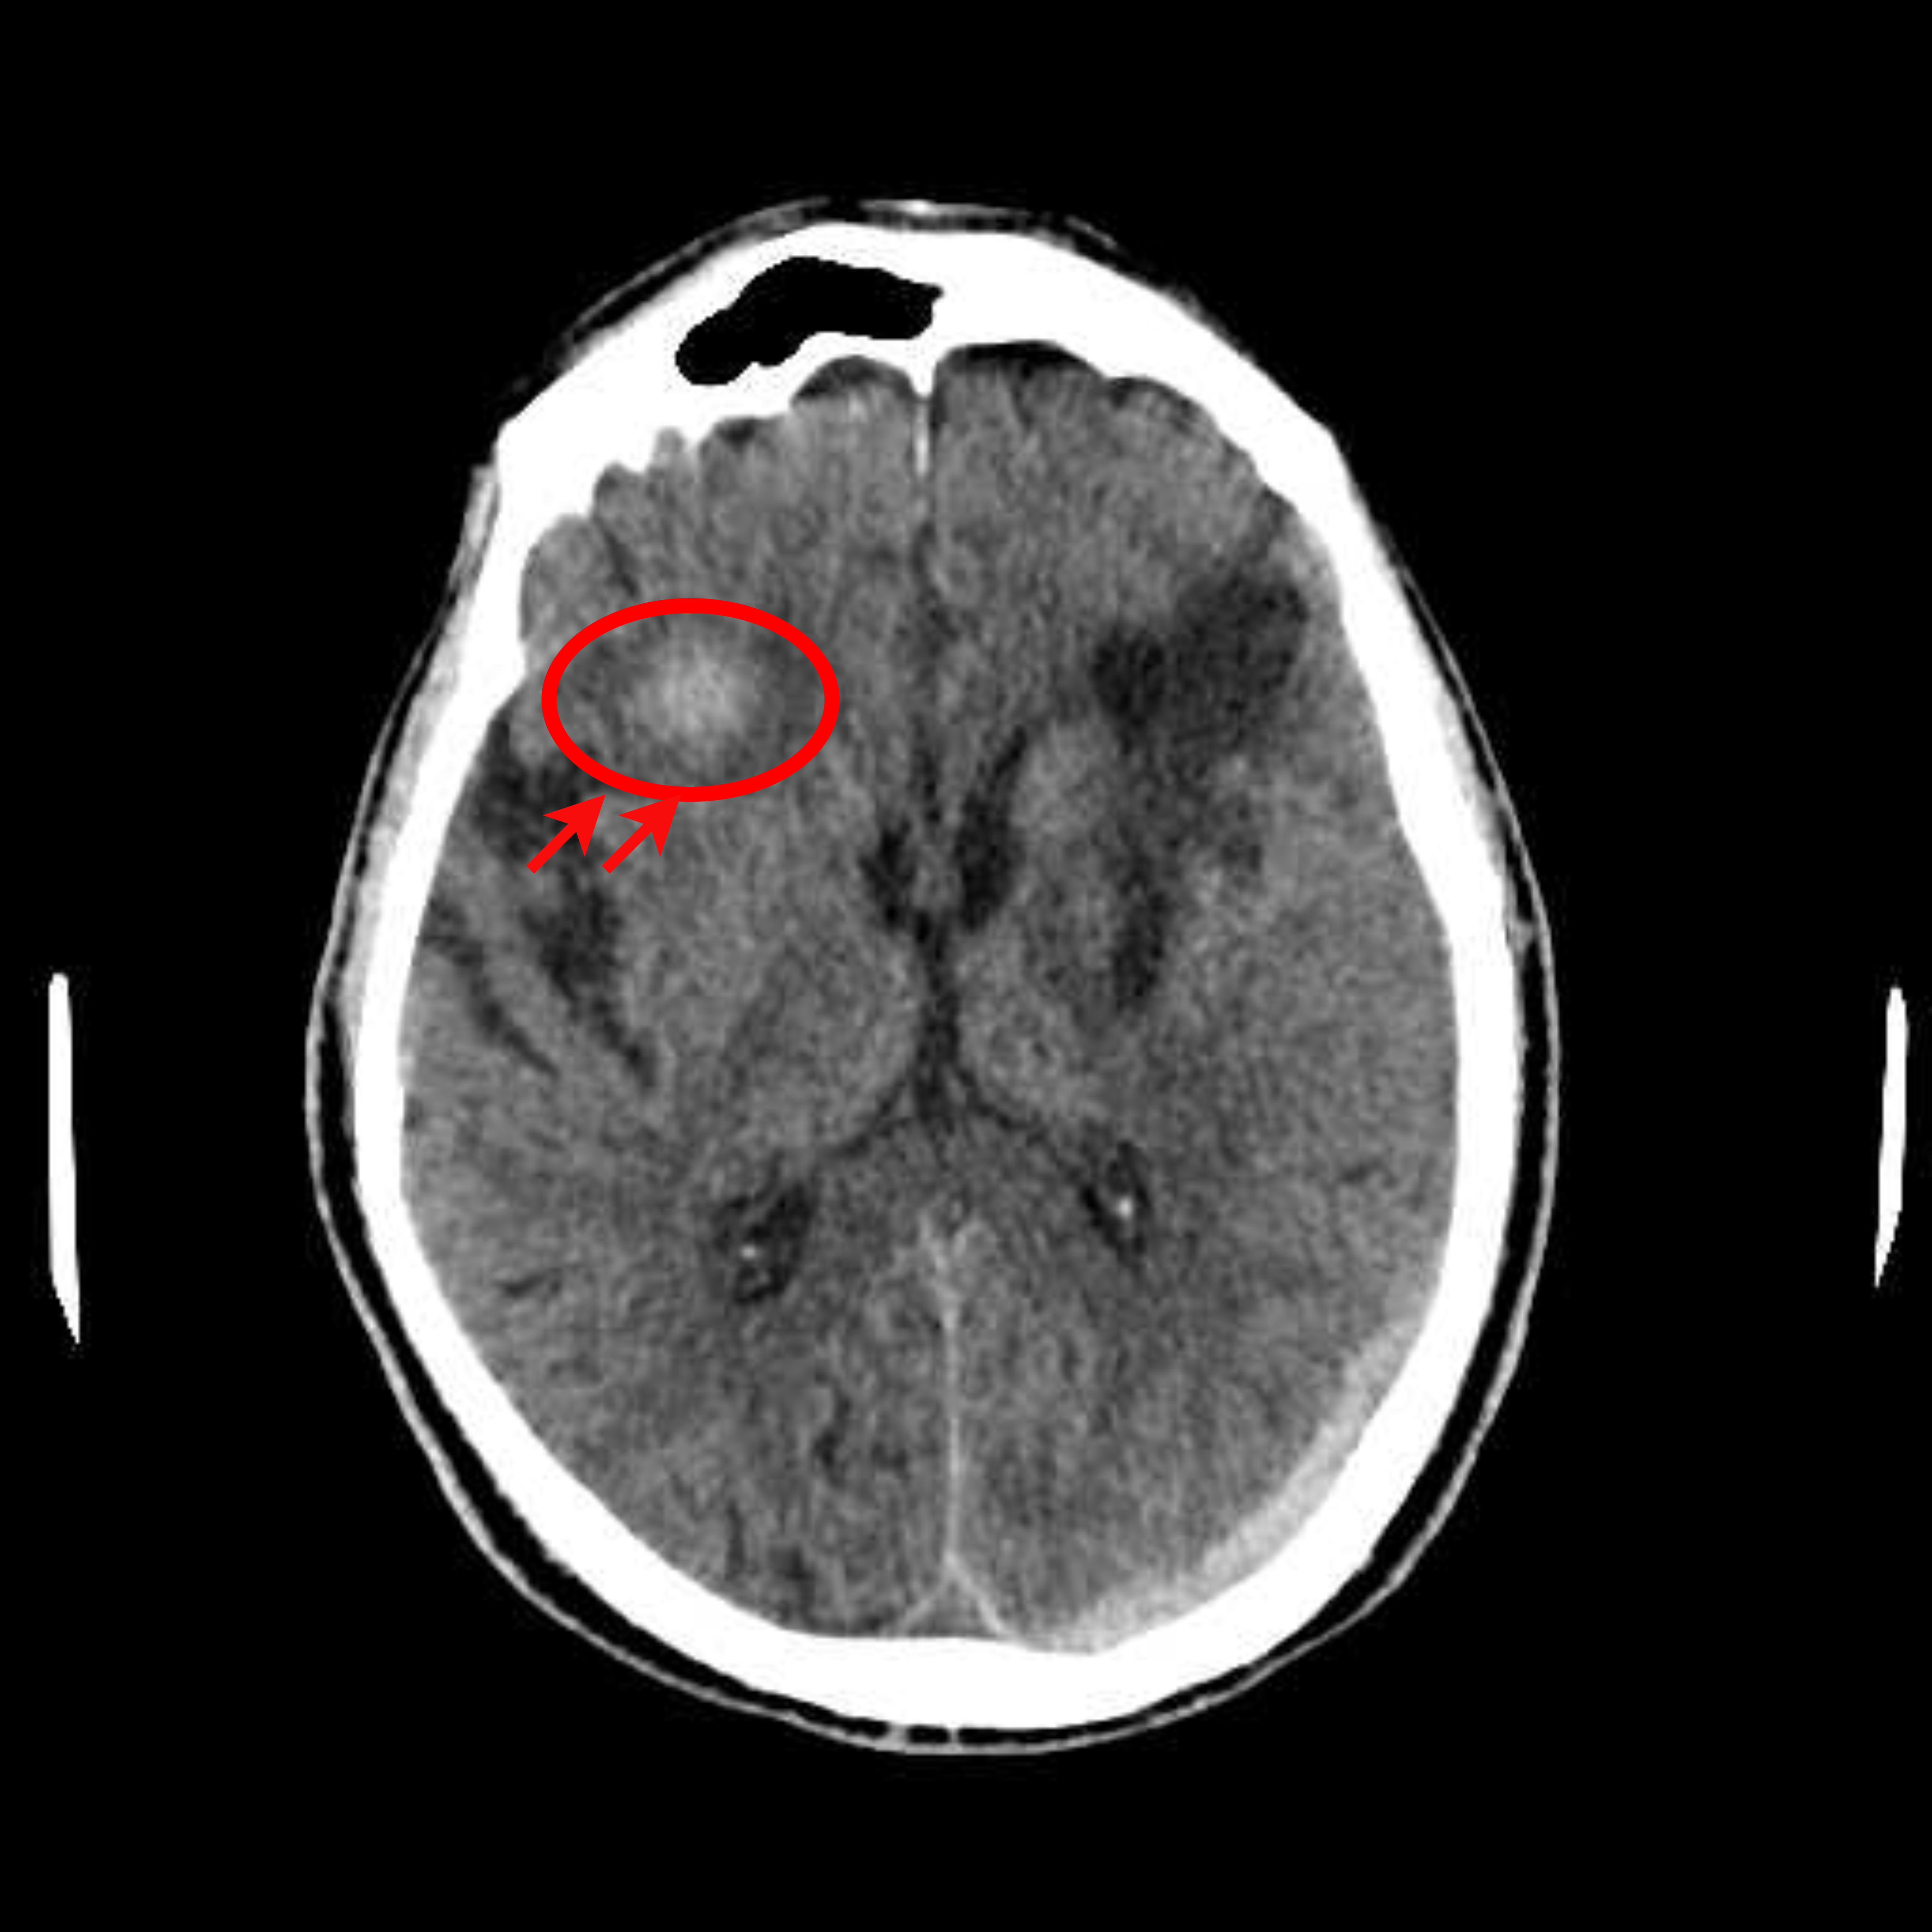

Figure 1: Illustrative examples of different types of brain hemorrhages in CT scans. The hemorrhagic regions are highlighted in red. (a) IPH, (b) IVH, (c) EDH, (d) SAH, (e) SDH.

The dataset used in this study was collected from two medical centers in Tehran, Iran: Rasoul Akram Hospital and Firouzabadi Hospital, over a period spanning 2018 to 2024. All CT scans were manually labeled hierarchically by two board-certified neurosurgeons to ensure accurate classification of ICH subtypes. The labeling process involved an initial annotation by one neurosurgeon, followed by validation and verification by a second expert to minimize errors and inconsistencies. Fig. 1 illustrates representative examples of different ICH subtypes in brain CT scans. The hemorrhagic regions are highlighted in red for better visualization. These annotated examples provide insight into the distinct imaging characteristics of each hemorrhage type, emphasizing the variability in their locations and appearances within the brain. The study received ethical approval, and data collection was conducted in compliance with institutional review board (IRB) regulations and the Declaration of Helsinki, ensuring patient confidentiality and adherence to ethical standards.